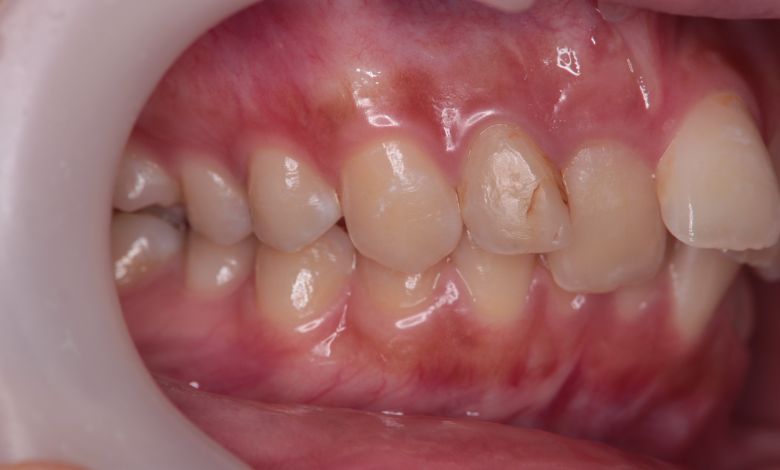

他院にて上下左右4本の抜歯を前提とした矯正治療を提案されていました。上顎・下顎ともに歯列弓が狭く、

V字型の弓状を呈していたため、叢生(歯の重なり)が強く、噛み合わせにも不調和が見られる状態でした。

上顎歯列はV字型に近く、全体的にアーチが狭窄している状態

上下の咬合関係も不正で、機能的にも審美的にも問題のある状態でした

歯列弓はV字型に狭く、左右の犬歯が唇側に大きく転位している状態